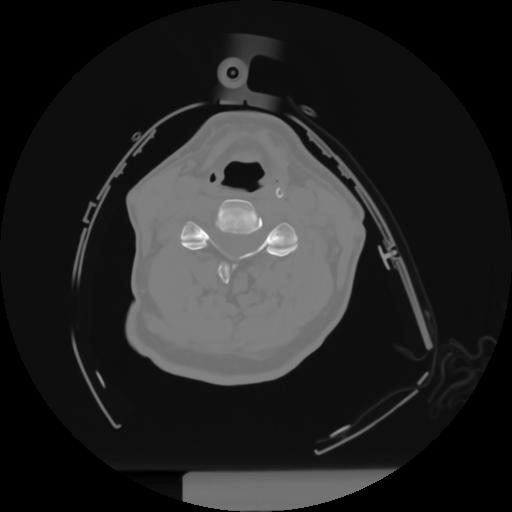

10 P.BLANDAS,,Axial,2.0,P.BLANDAS,,